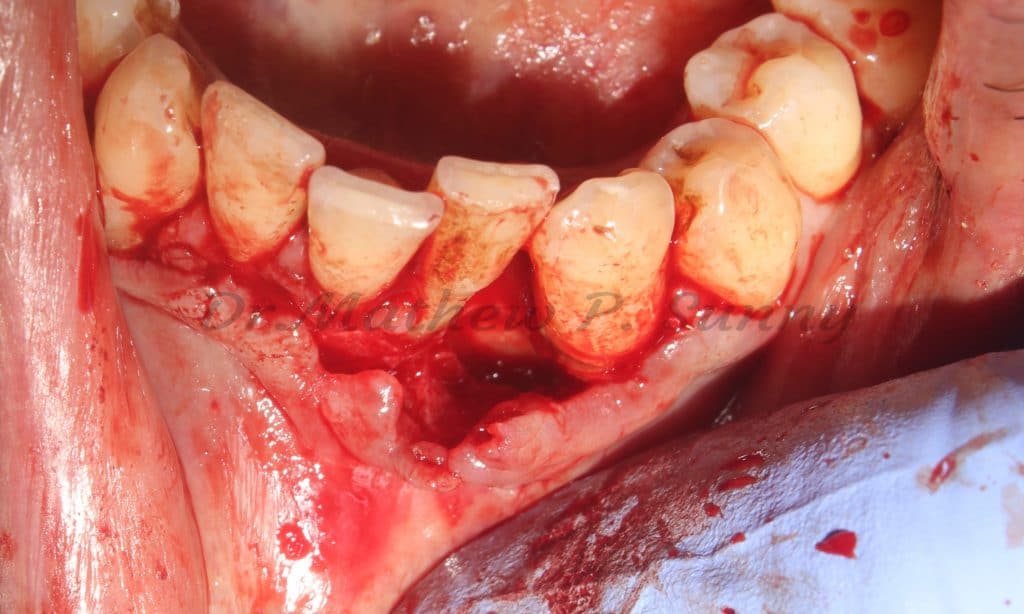

This patient presented with pain and swelling in relation to his lower left canine and lateral incisor.

Calculus was ++

Clinical presentation showing swelling in relations to the lower left canine and lateral incisor..

flap raised..

bone defect noted.. and all granulation tissue curreted..

subgingival calculus is noted and then removed..